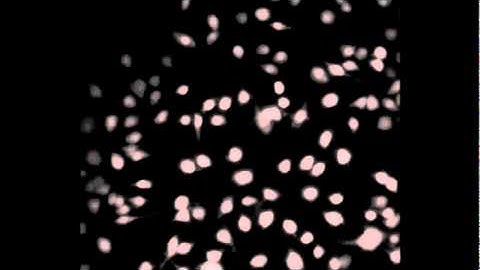

PCO-EDGE Sequence